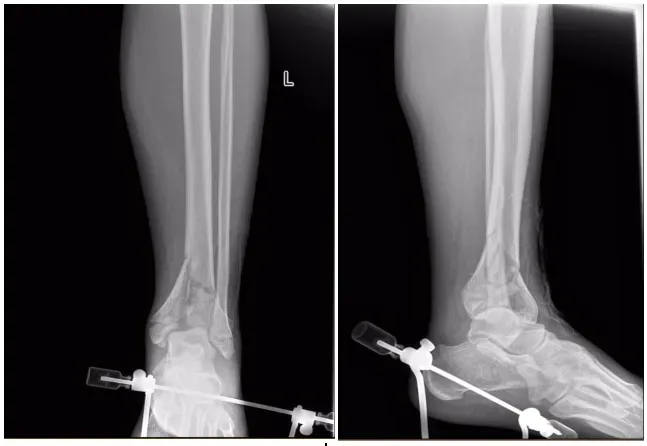

首先遵循损伤控制骨科(DCO)原则,团队第一时间开展紧急处置:实施即刻跟骨牵引,通过精准外力牵拉恢复肢体长度,缓解骨折端对周围血管、神经的压迫;搭建跨踝关节外固定架,对不稳定的踝关节进行临时固定,避免骨折移位加重软组织损伤;采用超声实时监测骨筋膜室压力,动态掌握肢体内部张力变化,严防骨筋膜室综合征。